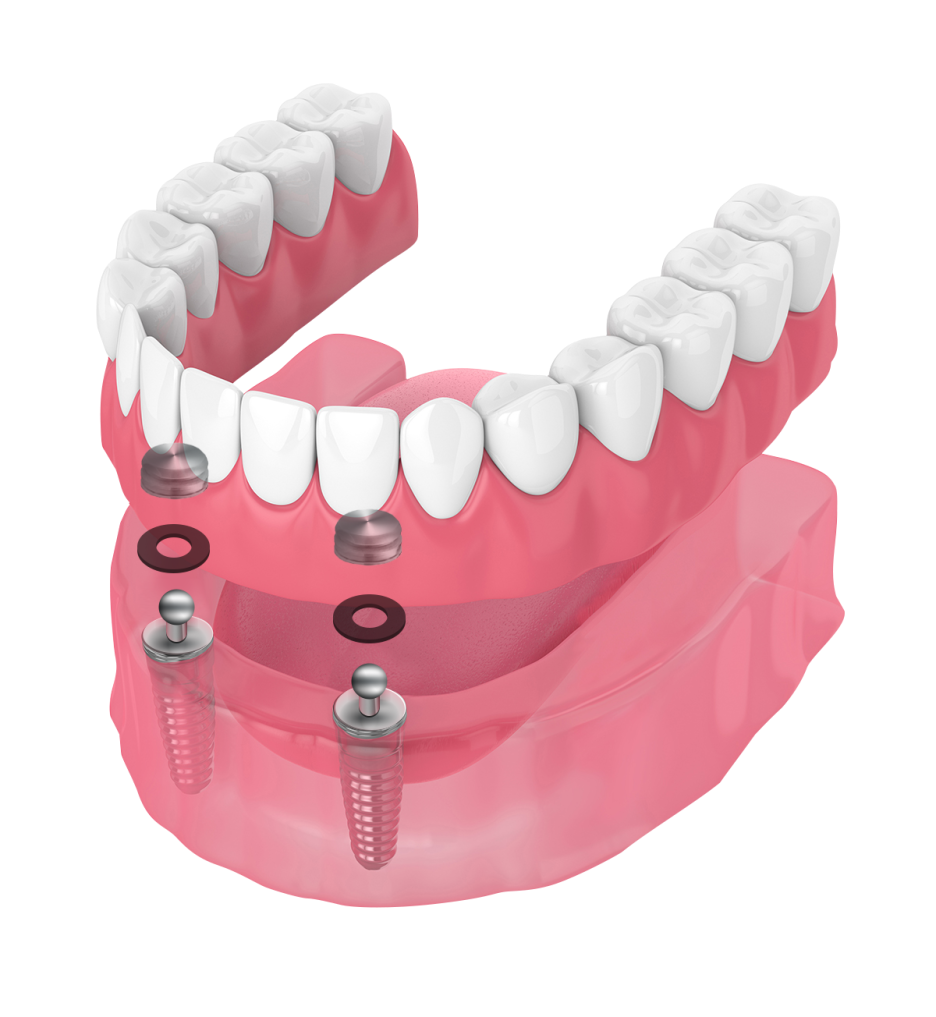

개념부터 정확히 설명드리자면

위 사진처럼 임플란트와 틀니 내면에

이 둘을 결합할 수 있는 로케이터를 달아

탈부착이 가능하도록 하는 방식을 뜻합니다.

(로케이터를 기억하시기 쉽게

똑딱이라 표현하다 보니 이런 이름이 붙었네요.^^)

아무래도 그냥 잇몸에 바로 올려두는 것보다

단추로 연결되다 보면

유지력이 조금 더 높아집니다.